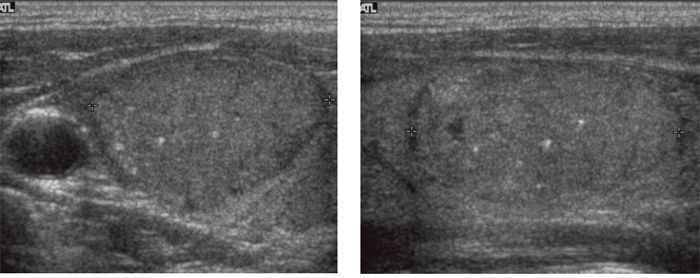

Figure 1: A 44-year-old man with a papillary thyroid carcinoma without any mutation in right thyroid lobe. Transverse (A) and longitudinal (B) ultrasonographic images show a 3.0-cm solid mass with circumscribed margin, oval-to-round shape, isoechogenicity, parallel orientation, and microcalcifications. This mass was classified as K-TIRADS category 4. After surgery, there was no lymph node metastasis and TNM stage was classified as I. There was no recurrence during 10.9 years of follow-up.